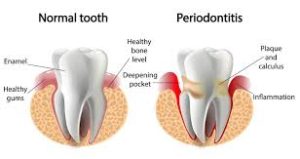

La Parodontite, conosciuta anche come Piorrea è un processo infiammatorio irreversibile a carico dei tessuti di sostegno dei denti.

Colpisce l’osso, il legamento parodontale e la gengiva che accoglie il dente e se non è intercettata in tempo, può causare anche la perdita dei denti. Essa è causata da una serie di fattori e quelli più importanti sono la placca batterica (in assenza della quale non esiste la malattia), il fumo e il diabete.

Di solito i primi sintomi compaiono in caso di gengive gonfie ed arrossate che sanguinano facilmente quando ci si lava i denti. In alcuni casi questa condizione potrebbe portare alla formazione di tasche gengivali, che causano con il tempo un indebolimento dei denti ed infiammazione del tessuto osseo sottostante, con sintomi in genere dolorosi. Anche l’abbassamento dell’osso alveolare è un sintomo chiaro della presenza di piorrea con il cattivo odore dell’alito, che diventa una ulteriore riprova.